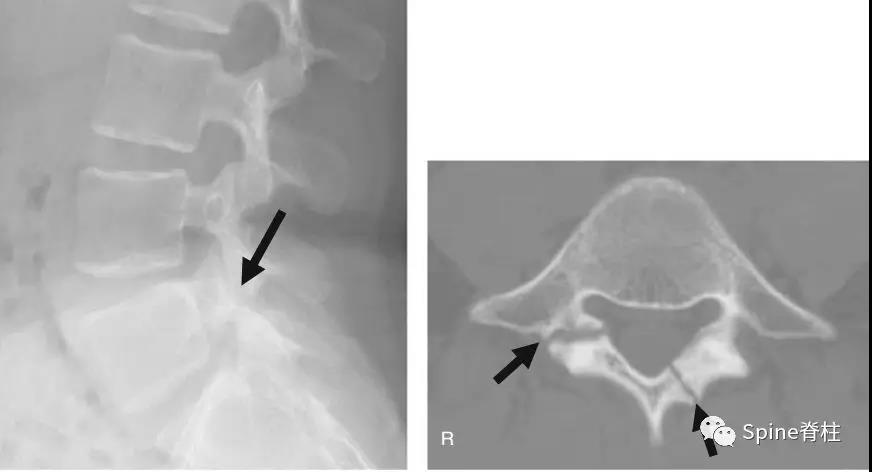

图:L5半椎板裂

17岁芭蕾舞者,腰痛7个月

CT示:左侧为椎板裂(箭头),右侧为峡部裂(箭头)

图:L5半椎板裂15岁篮球运动员,严重腰痛,影响睡眠CT示:左侧为椎板裂(箭头),右侧为峡部裂(箭头)